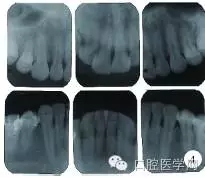

2013年1月,患者因前牙區(qū)牙齦腫脹伴刷牙出血就診于北京協(xié)和醫(yī)院口腔科,行下前牙區(qū)牙齦組織活檢,切片示上皮下炎癥性的纖維組織增生,血涂片檢查未見(jiàn)確切異常,行洗牙治療后自覺(jué)牙齦腫脹緩解不明顯,1個(gè)月后就診于北京大學(xué)口腔醫(yī)院牙周科,口內(nèi)檢查發(fā)現(xiàn)全口牙齦乳頭普遍紅腫增生,質(zhì)地韌,上、下前牙區(qū)尤為明顯(圖3A)。牙周探診深度(probing depth,PD)普遍4~7mm,中等量菌斑,探及大量齦下牙石,探診出血74.0%。全口根尖片顯示普遍的牙槽骨輕度吸收(圖4)。